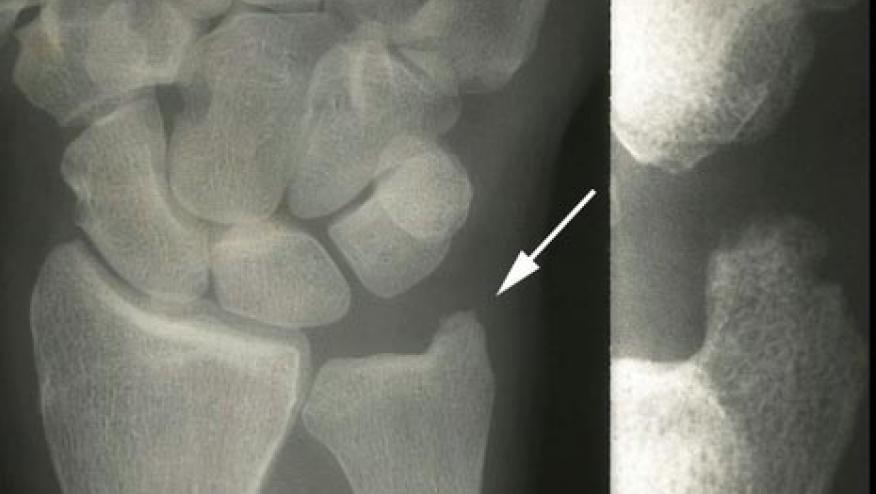

The DRIVE study was a multicenter, randomized, double-blind, placebo-controlled, phase II study in Japan, conducted over 12 months. Japanese patients who had RA were randomized in a 1:1:1:1 ratio to receive one of four treatments: a placebo; denosumab 60 mg every 6 months (Q6M); denosumab 60 mg every 3 months (Q3M); or denosumab 60 mg every 2 months (Q2M). Radiographs at baseline, 6 and 12 months were submitted to the central analyzing center (Synarc, California, USA) for Modified Sharp score evaluation.

Denosumab significantly inhibited the progression of bone erosion at 12 months. The mean changes of the modified Sharp erosion score at 12 months from baseline were as follows:

- 0.27 in denosumab Q6M

- 0.14 in denosumab Q3M (p=0.0082)

- 0.09 in denosumab Q2M (p=0.0036)

- 0.99 in the placebo (p<0.0001).

Meanwhile, modified Sharp JSN (Joint Space Narrowing) score did not differ between denosumab and placebo groups.